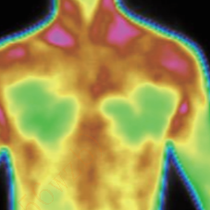

Application of Infrared Thermal Imaging in Healthcare

The human body is a natural biological heating element, and its heat radiation implies a lot of health information. Therefore, the change of the human body temperature is one of the important indicators for diagnosing cases. Medical infrared thermal imaging is a whole-body thermal imaging technology that passively receives the heat source of tissue cell metabolism of the human body. It can receive the human body heat radiation that cannot be seen by the human eyes, and objectively and accurately present the temperature distribution images of parts of the body, offering a reliable basis for clinical diagnosis.

In case of lesions in human blood vessels, blood circulation will be obstructed, and the temperature of the skin with lesions will decrease. The medical thermographic cameras can quickly display the temperature distribution images of the body parts to clearly determine the lesions, providing a reliable basis for clinical diagnosis.

Abnormalities of structural characteristics identified on the breast thermal images are associated with diseases and cell activity. In different disease courses of the tumor tissue, there are significant characteristics of cell metabolism. With the aid of analyzing the infrared thermogram, early auxiliary screening can be achieved, and preventive and treatment measures can be taken earlier.

It can form the temperature distribution image of the human body by obtaining the infrared radiation signals of different strengths of body parts. It can assist in syndrome differentiation in TCM, physical assessment in TCM, meridian point exploration and treatment effect evaluation. In terms of treatment effect evaluation, it is possible to specify the location, onset time, duration and effect degree of drugs, acupuncture or other treatment methods, objectively and accurately evaluating treatment methods.

When muscles are injured or inflamed, neuropathy and other symptoms cause locally poor blood flow and nerve conduction, all of which will cause abnormal expression of body metabolism. Medical thermographic cameras can accurately detect pain spots and inflammation areas, as a grading diagnosis of pain, accordingly, they can give a targeted treatment plan.